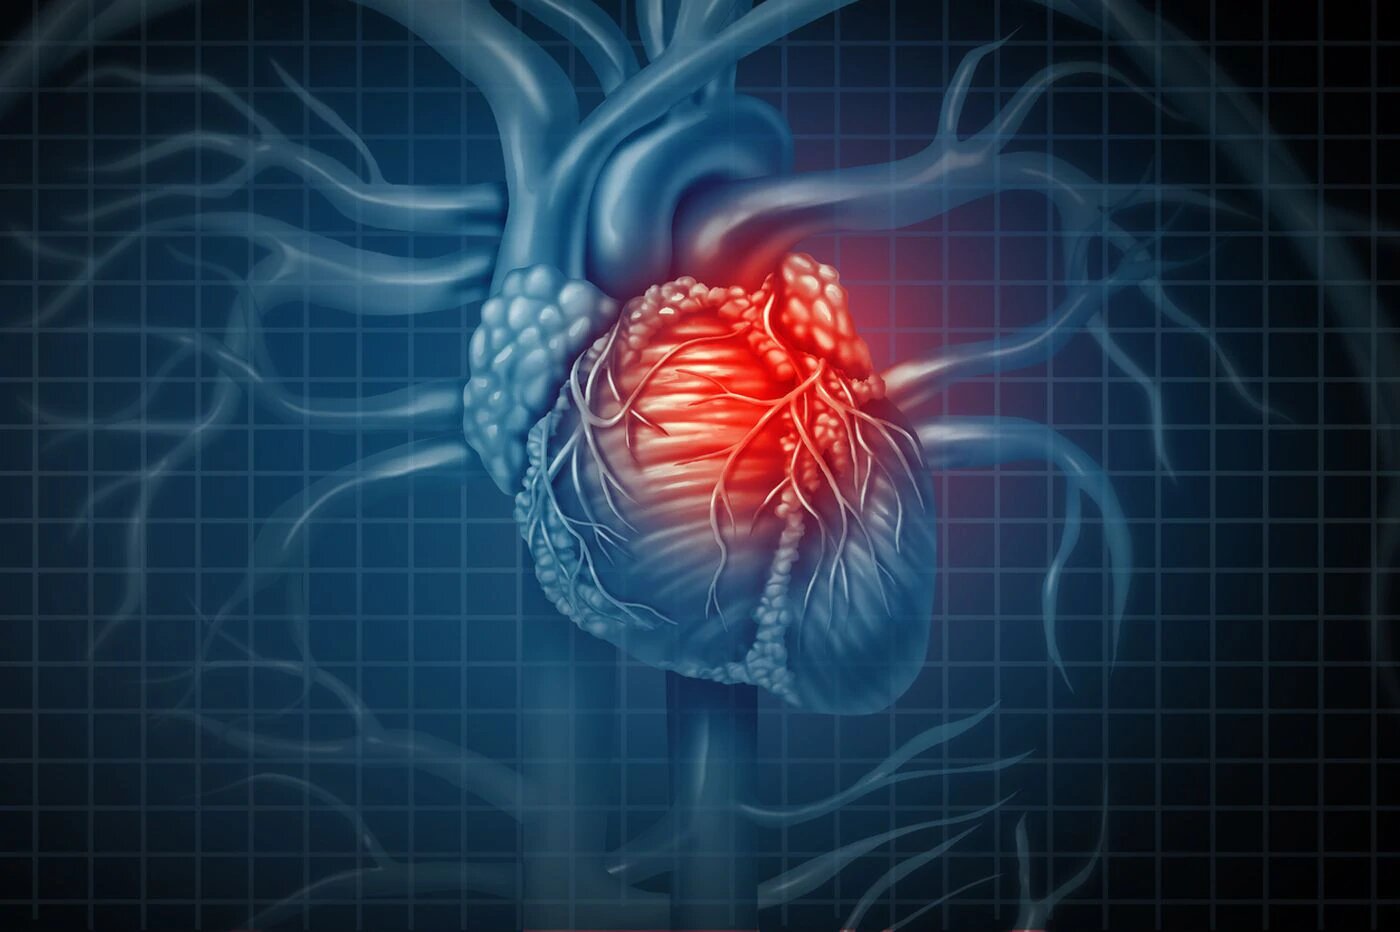

2- پاره شدن ناگهانی پلاک چربی و ایجاد لخته خون

در مواقعی اتفاق می افتد که رسوب چربی خون در حدی نیست که بتواند مانع جریان خون شود و به همین دلیل فرد بیمار هم در زمان فعالیت فاقد ناراحتی و درد قلبی است ولی پلاک چربی به صورت ناگهانی پاره می شود و محتویات داخل آن به صورت کلسترول و سلول های التهابی وارد جریان خون می شوند که این امر می تواند باعث تشکیل لخته خون داخل رگ قلب و انسداد ناگهانی آن شود. قطع ناگهانی جریان خون به عضلات قلبی می تواند به حمله حاد قلبی و اصطلاحا " سکته قلبی" منجر شود.